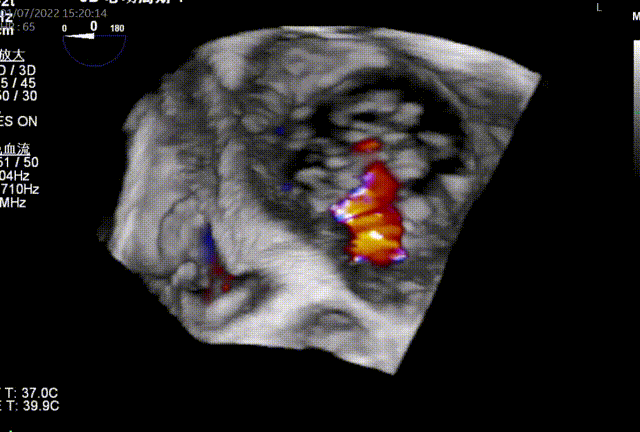

图3:术后即刻TEE

同时其夹子系统继承于申淇淇麟®-经导管二尖瓣夹及可操控导引导管系统优秀设计,具备四个不同型号的夹子及瓣叶分开捕获能力,从而适用于更加复杂多变的三尖瓣解剖。因该患者三尖瓣反流束较宽,瓣叶存在较宽的关闭裂隙,术中很好的利用了瓣叶分开捕获的功能,于前隔瓣区域行瓣膜缘对缘修复。植入一枚长宽夹子后,术后即刻患者反流减至轻度。患者术后恢复良好,出院前TTE提示三尖瓣轻度反流。